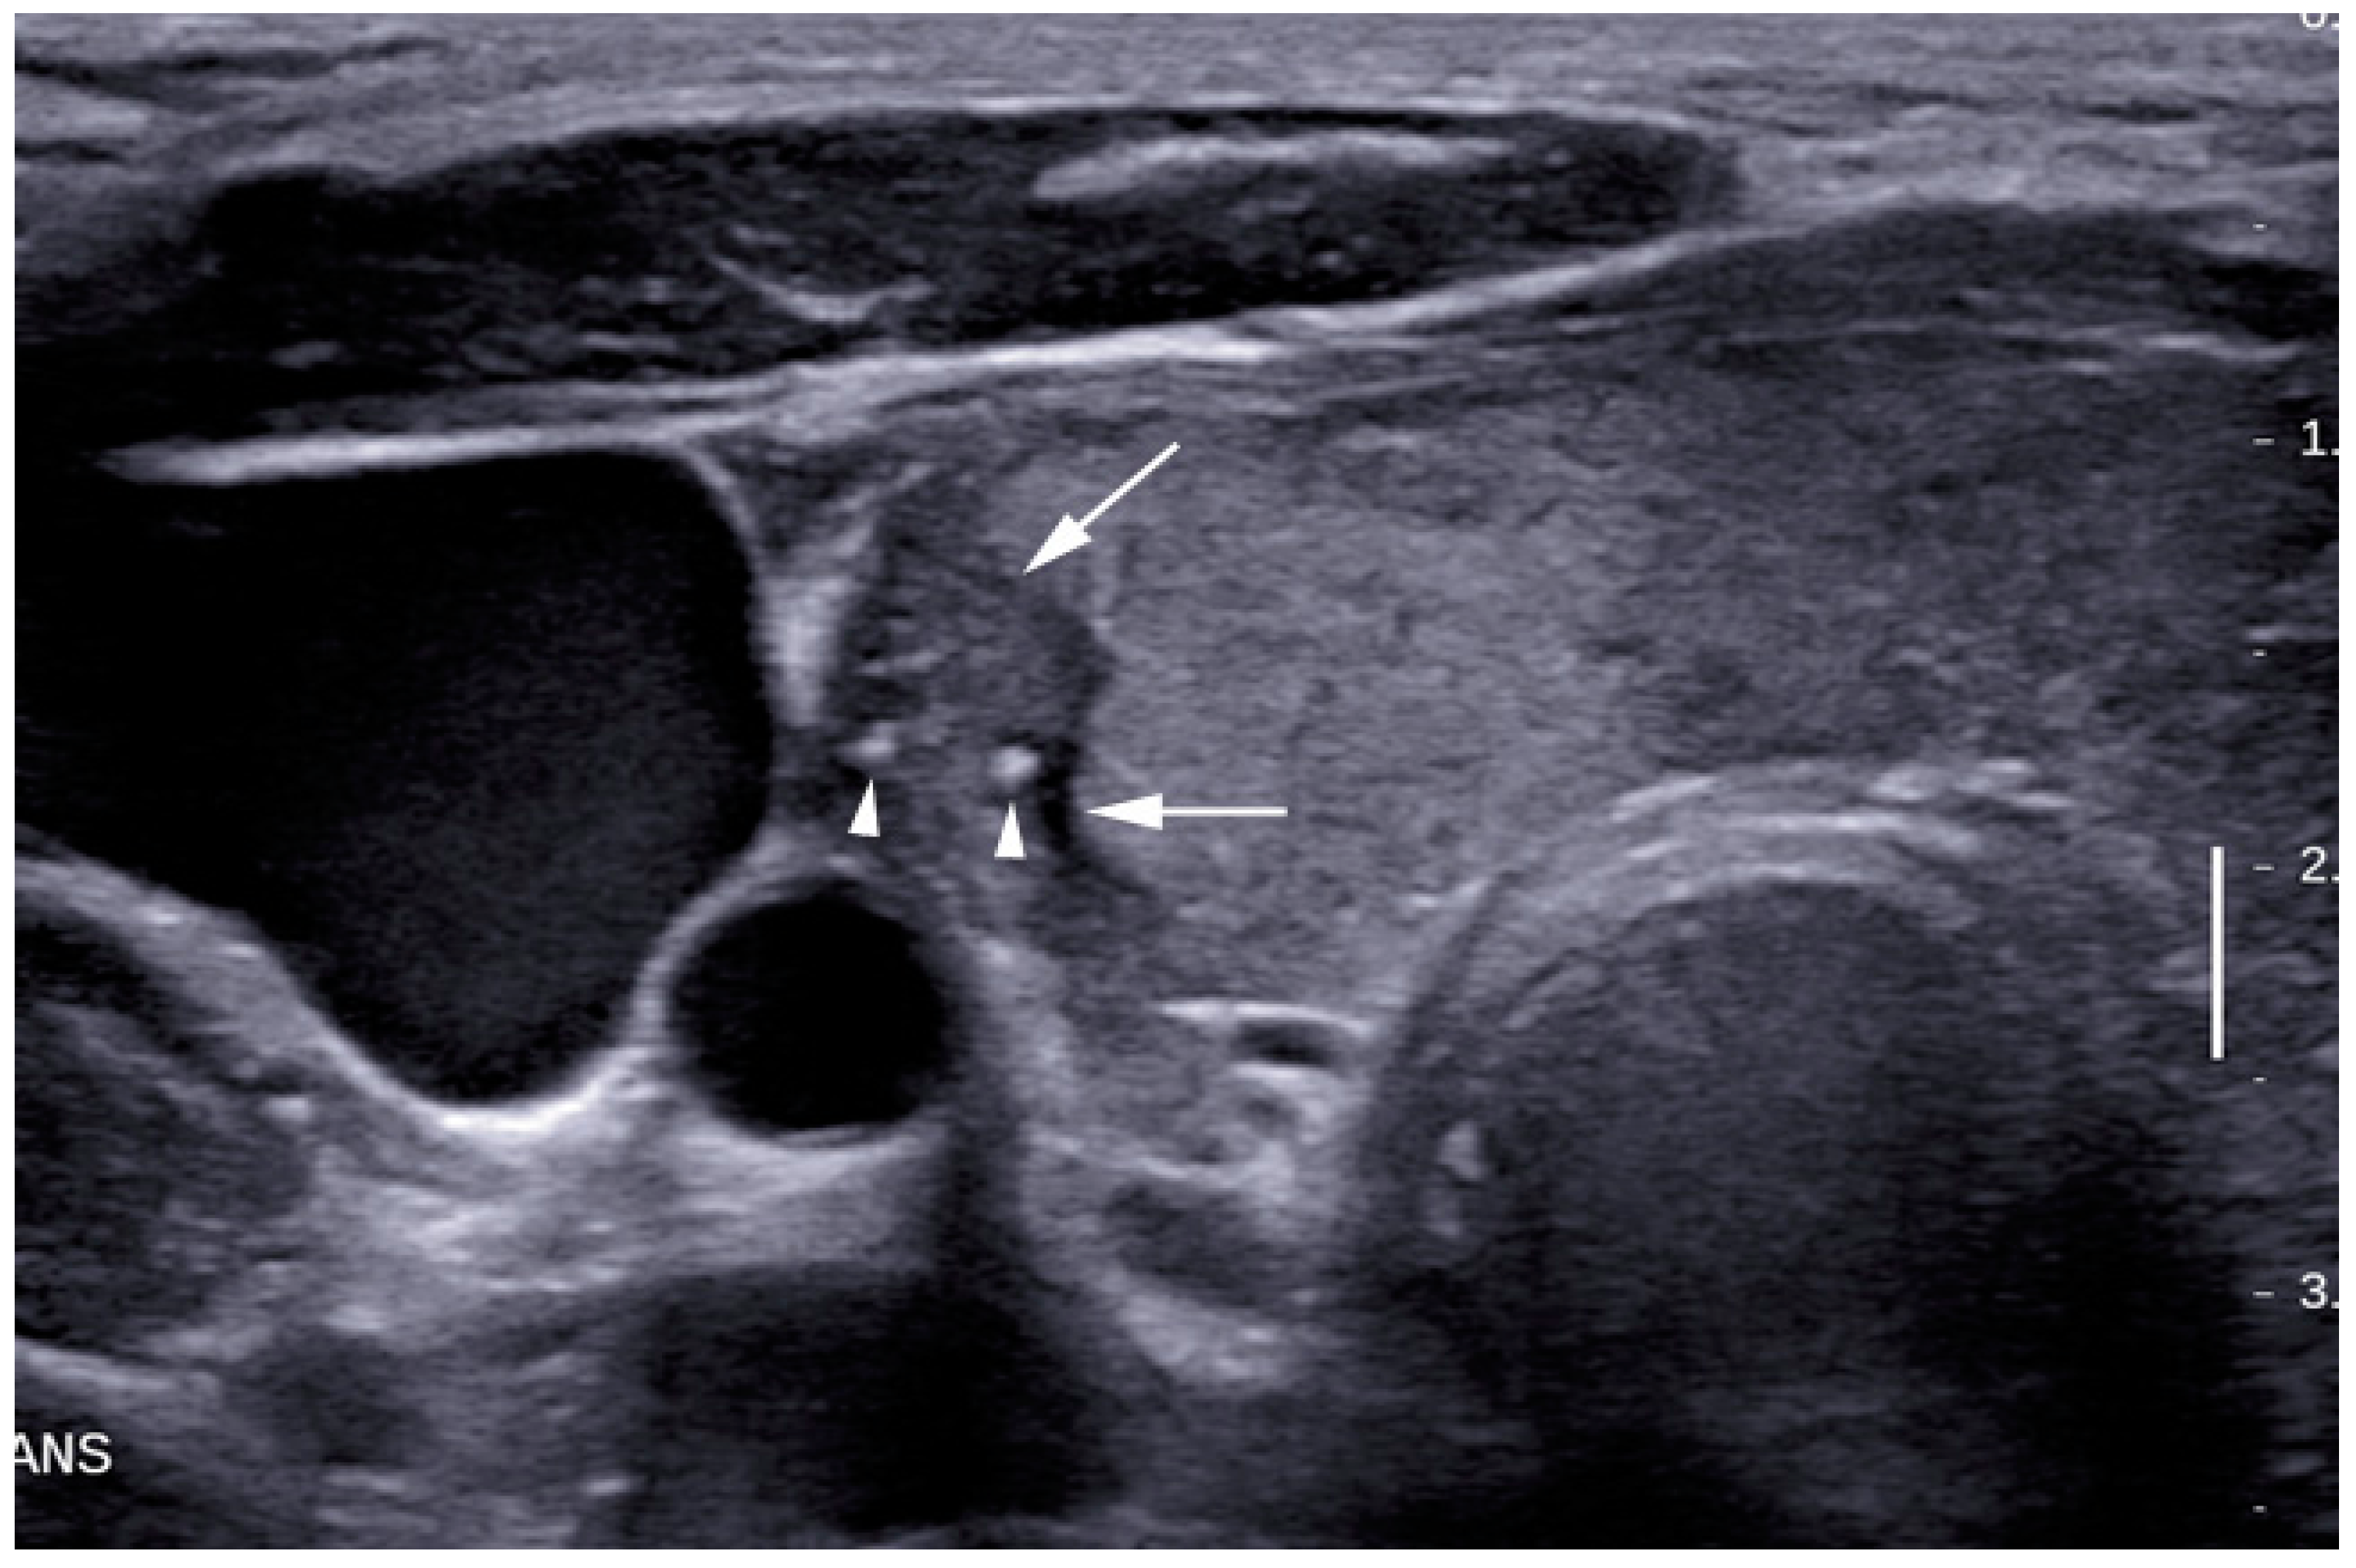

| Microcalcification | |||

| Yes | 6 (7.1%) | 21 (77.8%) | <0.05 |

| No | 78 (92.9%) | 6 (22.2%) | (0.12–0.49) |

| Tall/width ratio >1 | |||

| Yes | 11 (13.1%) | 16 (59.3%) | <0.05 |

| No | 73 (86.9%) | 11 (40.7%) | (0.29–0.74) |

| Hypoechogenicity | - | - | - |

| Yes | 28 (33.3%) | 25 (92.6%) | <0.05 |

| No | 56 (66.7%) | 2 (7.4%) | (0.42–0.71) |

| Irregular margins | |||

| Yes | 14 (16.7%) | 15 (55.6%) | <0.05 |

| No | 70 (83.3%) | 12 (44.4%) | (0.38–0.83) |

| Absent Halo sign | |||

| Yes | 74 (88.1%) | 26 (96.3%) | >0.05 |

| No | 10 (11.9%) | 1 (3.7%) | (0.65–1.01) |